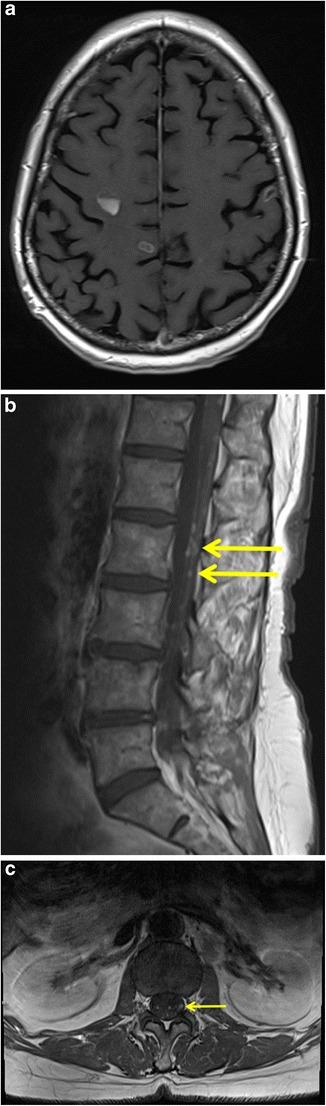

Lung cancer patients often experience potentially life-threatening medical urgencies and emergencies, which may be a direct or indirect result of the underlying malignancy. This pictorial review addresses the most common thoracic, neurological and musculoskeletal medical emergencies in lung cancer patients, including superior vena cava syndrome, pulmonary embolism, spontaneous pneumothorax, cardiac tamponade, massive haemoptysis, central airway obstruction, oesophagorespiratory fistula, malignant spinal cord compression, carcinomatous meningitis, cerebral herniation and pathological fracture. Emphasis is placed on imaging findings, the role of different imaging techniques and a brief discussion of epidemiology, pathophysiology and therapeutic options. Since early diagnosis is important for adequate patient management and prognosis, radiologists have a crucial role in recognising and communicating these urgencies and emergencies.

肺癌患者常经历可能危及生命的医学急症,这可能是潜在恶性肿瘤的直接或间接结果。本图像综述探讨了肺癌患者最常见的胸部、神经和肌肉骨骼医学急症,包括上腔静脉综合征、肺栓塞、自发性气胸、心脏压塞、大量咯血、中央气道阻塞、食管气管瘘、恶性脊髓压迫、癌性脑膜炎、脑疝和病理性骨折。重点介绍影像学表现、不同成像技术的作用,并简要讨论流行病学、病理生理学和治疗选择。由于早期诊断对患者的充分管理和预后很重要,放射科医生在识别和传达这些急症方面起着关键作用。

• 多平面多探测器计算机断层扫描是胸部急症的首选成像检查。• 磁共振成像(MRI)是调查中枢神经系统急症的首选成像方式。• 急症可能是肺癌的初始表现。• 放射科医生在识别和传达这些急症方面起着关键作用。